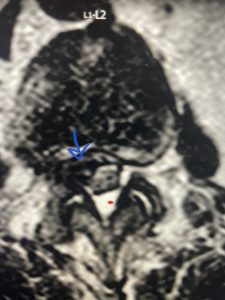

Epidural lipomatosis is a relatively rare condition where normally present fat in the epidural space is hypertrophied and can cause severe thecal sac compression. It is generally deposited more in the lateral and dorsal epidural space. This can be caused by long term steroid use and obesity, but also can be idiopathic. He had done well until more recently had developed low back pain with bilateral thigh pain and numbness. He had difficulty walking because of the pain. A new MRI (Fig 5) revealed that he had developed severe degeneration of the L1-2 segment above his prior decompression and fusion with a large extruded disc/osteophyte, right greater than left with severe thecal sac compression. He also had some residual T12-L3 residual epidural lipomatosis.

He had failed conservative treatment consisting of neurontin, physical therapy and epidural injections. He underwent revision laminectomy T12-L3 to decompress and explore prior fusion. He did have significant epidural fat encountered particularly at L1-2. The fat in epidural lipomatosis has a much more firm, globular texture. It takes a while to search within the fat, gently dissecting with a Penfield 4, to finally find the thecal sac! We encountered a large subligamentous extruded fragment lateral to the thecal sac on the right above the take off of the L2 nerve root. We removed any more residual fat at the L2-3 level and T12-L1 and decompressed the sac well. On exploration of the prior fusion it was fairly solid, but had some gaps at L2-3 fusion mass. Therefore we added a T12-L3 in situ fusion to augment those gaps and because we were at the thoracolumbar junction we extended fusion to T12. Post operatively he had relief of his leg pain.

(Figs 5a): Sagittal (a) and axial (b) T2-weighted lumbar MRI demonstrating status post lumbar decompression and insitu fusion L2-5 now well decompressed (blue dash) with development of new (red arrow) severe stenosis and with superimposed right L1-2 disc herniation (blue arrow)

(Figs 5b)